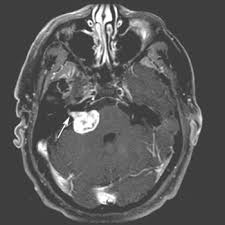

听神经瘤也叫“前庭神经鞘膜瘤”,是起源于前庭神经鞘膜的一种【良性】肿瘤,占颅内良性肿瘤的6%-8%,占桥小脑区肿瘤80%-90%。

听神经从脑干的听觉中枢分出来后经过“桥小脑区”,随后进入我们颞骨的一段狭窄而短小的“内听道”,并与耳蜗连接。

其次,随着瘤体增大,可以因为压迫其他邻近的神经出现相关症状,例如压迫三叉神经出现同侧面部的感觉迟钝和角膜反射减退;压迫小脑出现精细运动,协同运动障碍。

但最重要的,还是压迫与其相邻非常近、共同进入内听道的面神经,导致面瘫。而很多患者的首发表现也是面瘫,这也导致听神经瘤与面神经瘤的鉴别非常困难,只有通过手术切下来以后才知道,这个肿瘤是来源于听神经还是面神经。